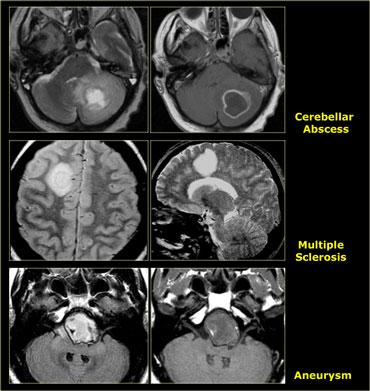

Các Tổn Thương Giả U

Nhiều tổn thương không phải u có thể bắt chước hình ảnh u não.

Áp xe có thể bắt chước hình ảnh di căn.

Bệnh xơ cứng rải rác có thể biểu hiện dưới dạng tổn thương giống khối có ngấm thuốc, còn được gọi là xơ cứng rải rác dạng u (tumefactive multiple sclerosis).

Tại vùng cạnh hố yên, cần luôn xem xét khả năng có phình động mạch.

Các bệnh lý nhiễm trùng và tổn thương mạch máu cũng có thể bắt chước hình ảnh u hệ thần kinh trung ương.